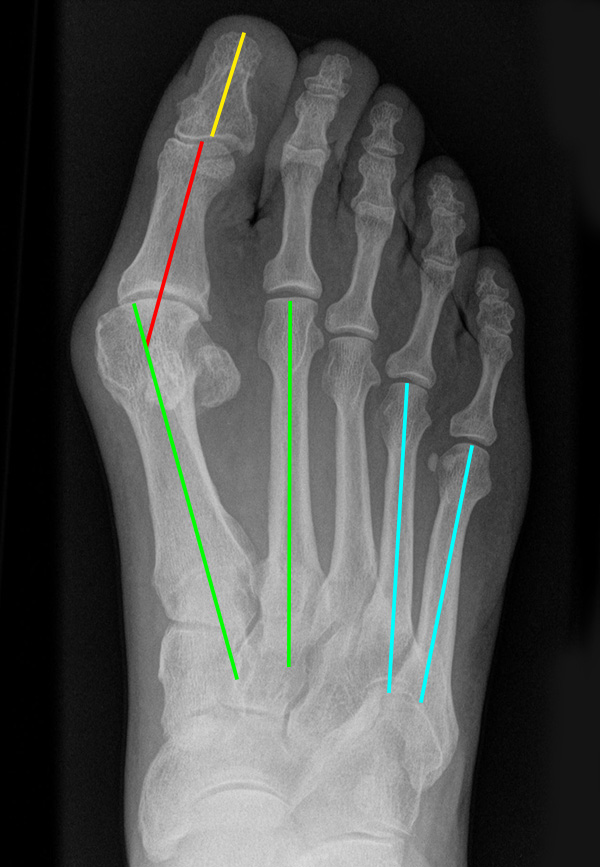

Eine Verbreiterung des Vorfußes wird als Spreizfuß bezeichnet. Ursächlich ist meist eine Deviation des ersten Metatarsale nach medial und/oder eine Abweichung des fünften Metatarsale nach lateral. Die Abweichung kann im Röntgenbild quantifiziert werden. Der Winkel zwischen Os metatarsale I und II wird als pathologisch zu bezeichnet, wenn er in der belasteten dorsoplantaren Röntgenaufnahme 9° überscheitet. Der Intermetatarsalwinkel IV/V wird ab einem Wert von mehr als 8° als erhöht.

Abbildung 16: Belastetes dorsoplantares Röntgenbild des Fußes. Zur Beurteilung des Spreizfußes wird der Intermetatarsalwinkel I/II (grüne Linien - Norm < 9 Grad) und der Intermetatarsalwinkel IV/V (blaue Linien - Norm < 8°) bestimmt. Die Abweichung der Großzehe ist durch den Hallux valgus Winkel definiert (grüne/rote Linie), eine Fehlstellung innerhalb der Großzehe durch den Interphalangealwinkel (rote/gelbe Linie) (M. Walther).